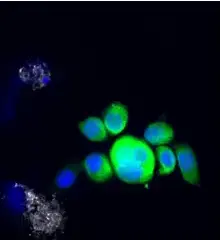

Example images from patient blood samples

Cluster of epithelial CTCs - breast

Examples of Portrait+ CTC staining kit samples